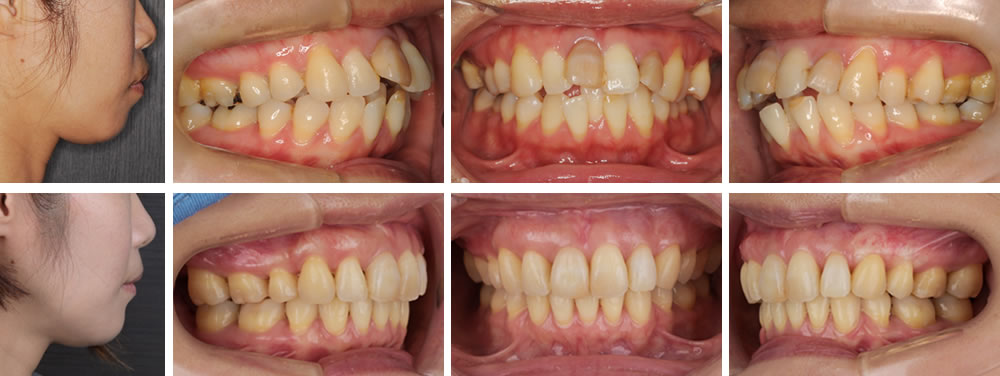

30代の女性です。歯のでこぼこと口元を気にされて来院されました。口元をスッキリさせたいとのはっきりとした依頼でした。

分析の結果、でこぼこの度合いが大きく上下の左右1本ずつを抜いて治療を行うことになりました。抜歯したスペースをすべて前歯を後方移動に使いたいため、歯科矯正用アンカースクリューを用いて行いました。治療後は口元がすっきりし、満足して頂けました。

歯茎が下がってしみているところには結合組織移植を行い、改善を行いました。